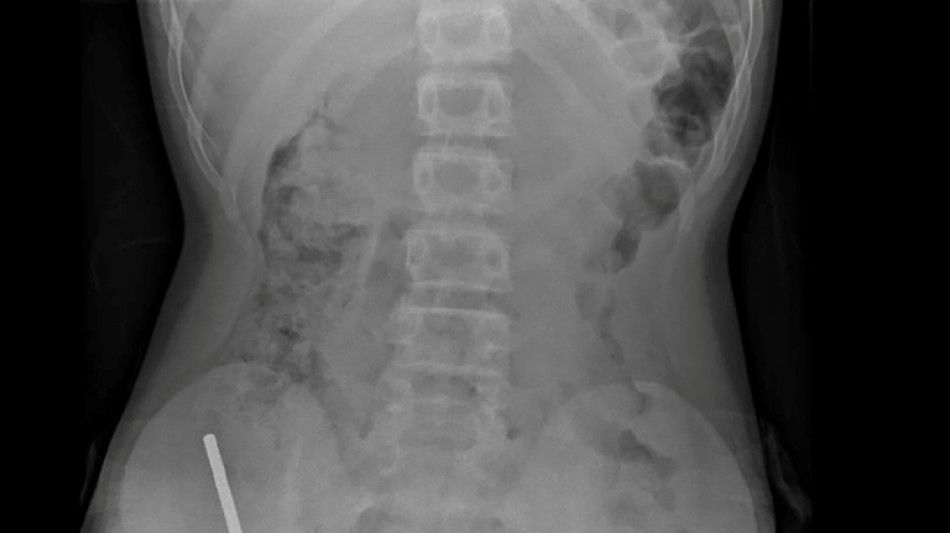

En Nouvelle-Zélande, un adolescent de 13 ans s'est vu retirer plusieurs parties nécrosées de ses intestins après avoir avalé près d'une centaine d'aimants achetés en ligne sur le site Temu, a rapporté vendredi une revue médicale.

"Il avoué avoir ingéré entre 80 et 100 aimants puissants au néodyme, de 5x2mm environ, une semaine plus tôt", indique un rapport des médecins de l'hôpital de cet hôpital, publié dans le New Zealand Medical Journal (NZMJ).

Les médecins ont déclaré que la pression exercée par les aimants avait provoqué une nécrose dans quatre zones de l'intestin grêle et du gros intestin du garçon.